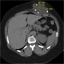

Suspicion for malpositioned ventriculoperitoneal shunt diagnosed with bedside ultrasound